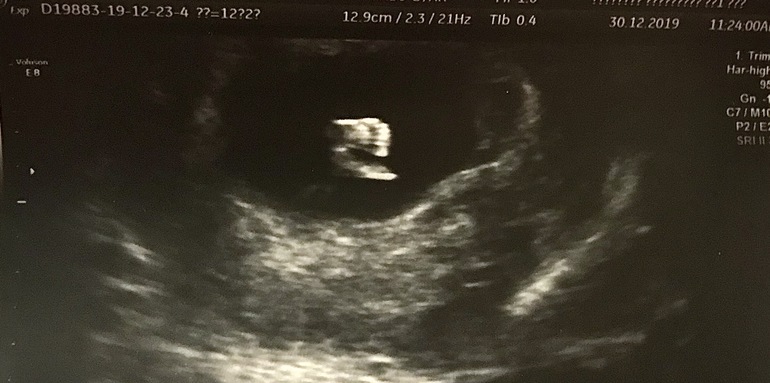

1-й скрининг в 12 недель и 2 дня

КТР уже 60мм, все показатели в норме, красивый носик ☺️ Малыш активно махал нам ручками 👋🏻

Получили чудесные фото на память и вот эта особенно милая 😍 Сладкие ножки